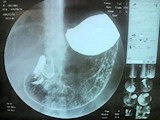

デジタル透視撮影装置

バリウムを使って胃や大腸のガンの検査や、尿管結石等の検査を行っています。